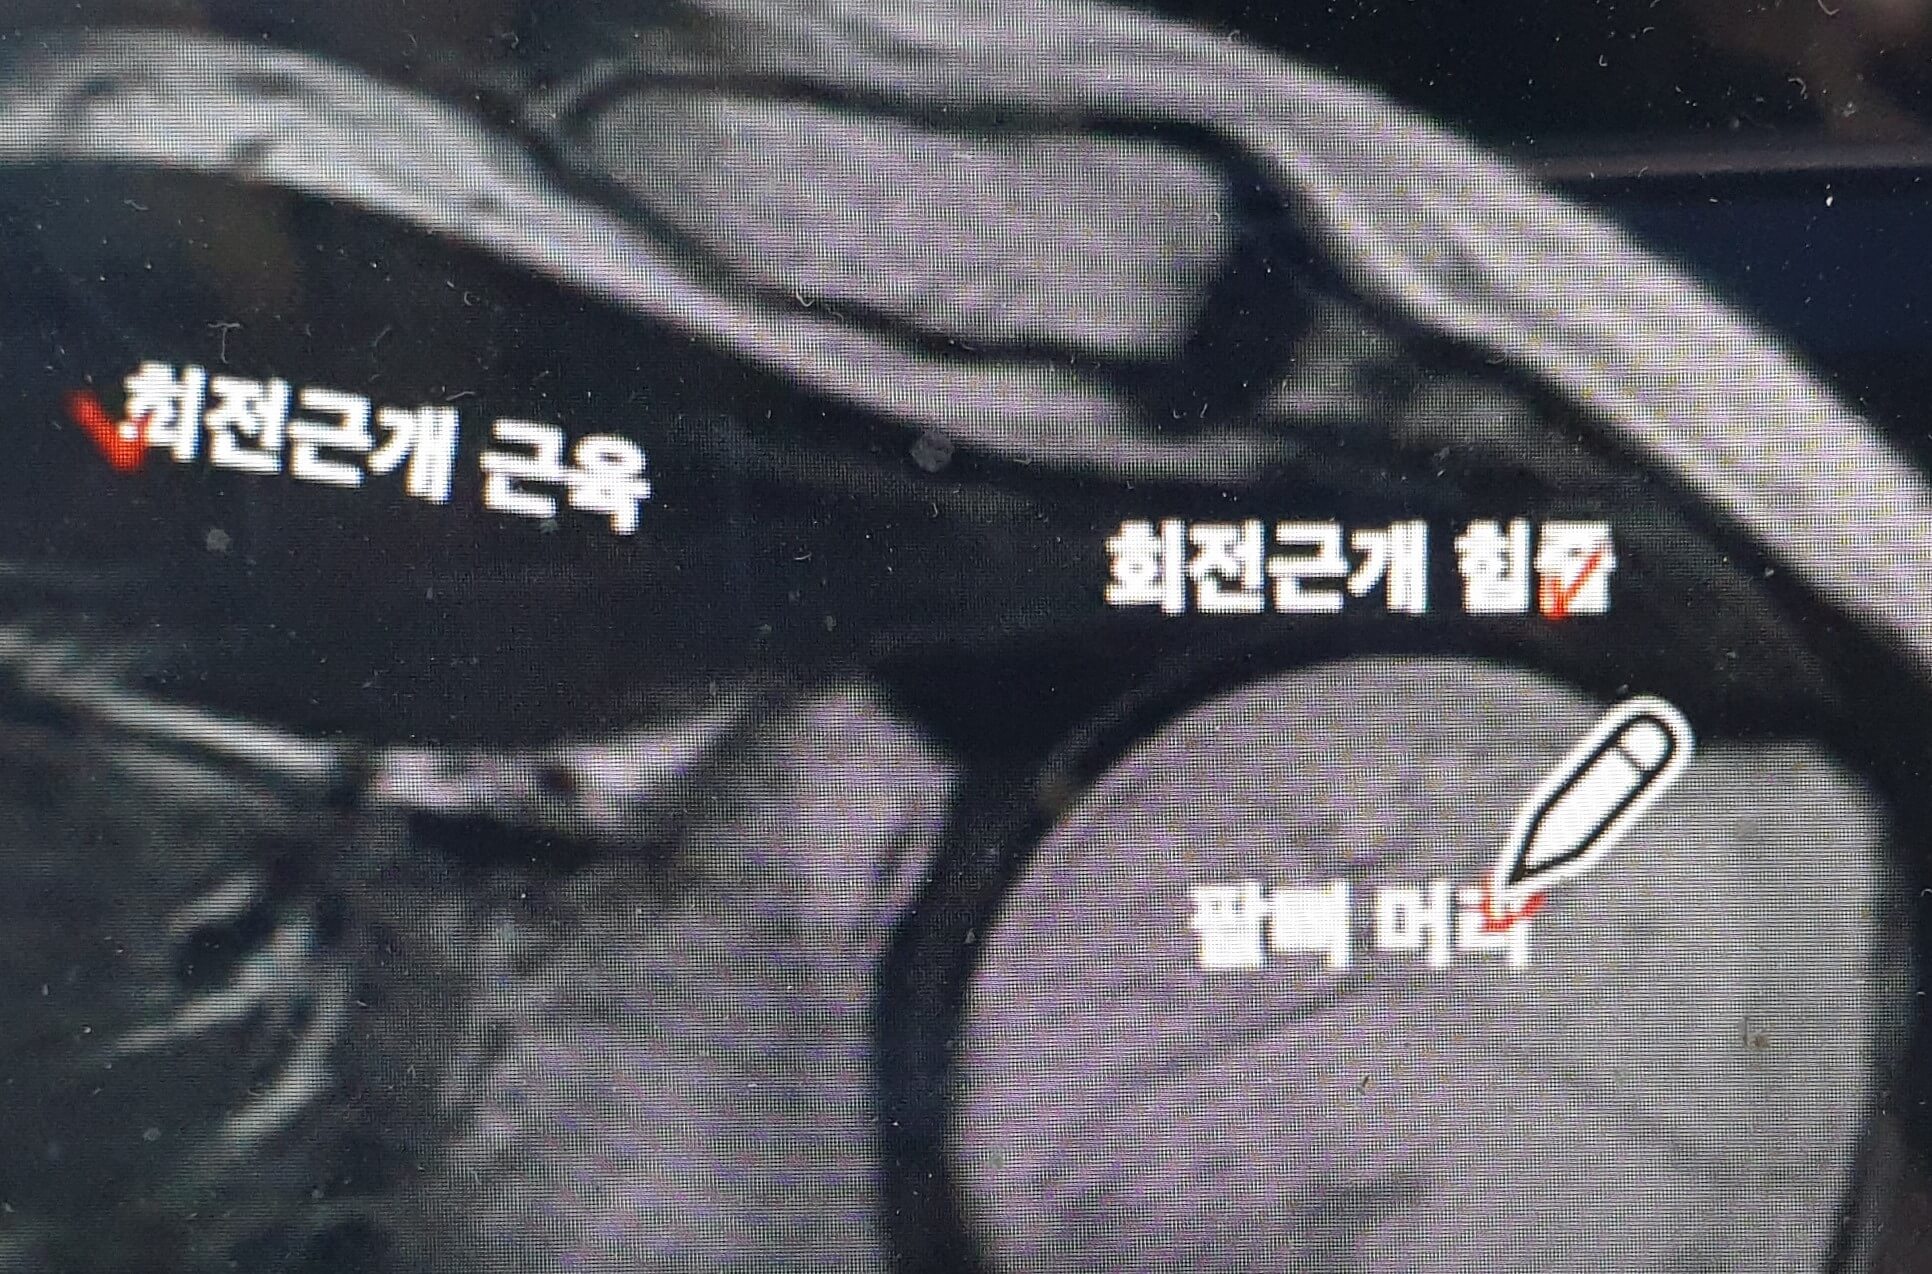

다음 사진은 어깨부위 MRI를 자세히 확대 놓은 것으로 회전근개 근육, 회전근개 힘줄, 팔뼈 머리부위가 보입니다.

실제 석회결절은 MRI에서는 검게 보여 힘줄이나 인대와 구별이 어렵다고 합니다.

이해가 쉽도록 석회결절을 하얗게 표현하였으니 참고하시면 됩니다.

위 사진상 화살표 방향으로 회전근개 힘줄 안에 석회결절이 시간이 지남에 따라서 변화하게 됩니다.